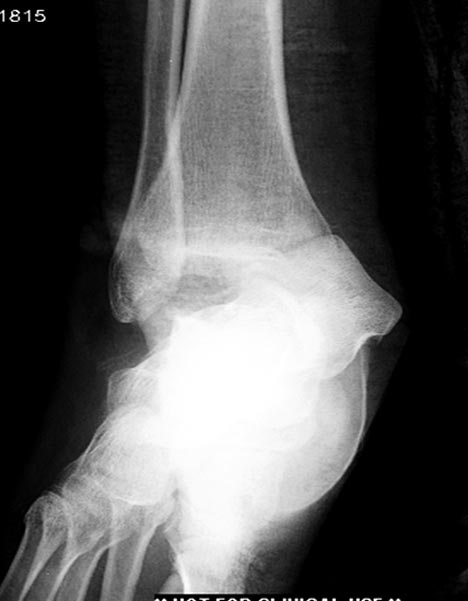

Здесь перечислены ортопедические повреждения: Rt. femoral shaft fracture, Rt femoral head fracture-dislocation, Rt distal femur fracture, Rt. open patella fracture, Rt. talus fracture dislocation, Rt. open humerus fracture, Left 5th metatarsal fracture, Left dislocation 1st TMT.

6 день госпитализации-операция на таранной кости.

На 9й день фиксация дистального бедра, где фрагмент Hoffa и вертикальный перелом надколенника, зафиксированы винтами.